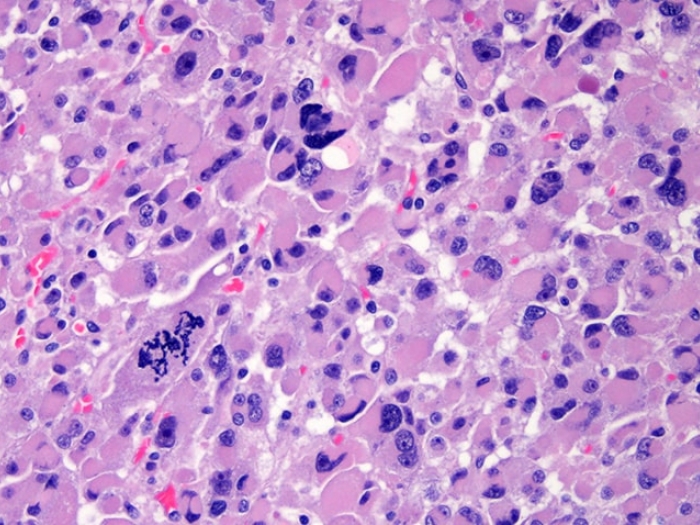

Detecting When the Most Common Skin Cancer Turns Dangerous

A University of Michigan study finds a biomarker associated with basal cell carcinoma may help signal which skin tumors will be more aggressive.